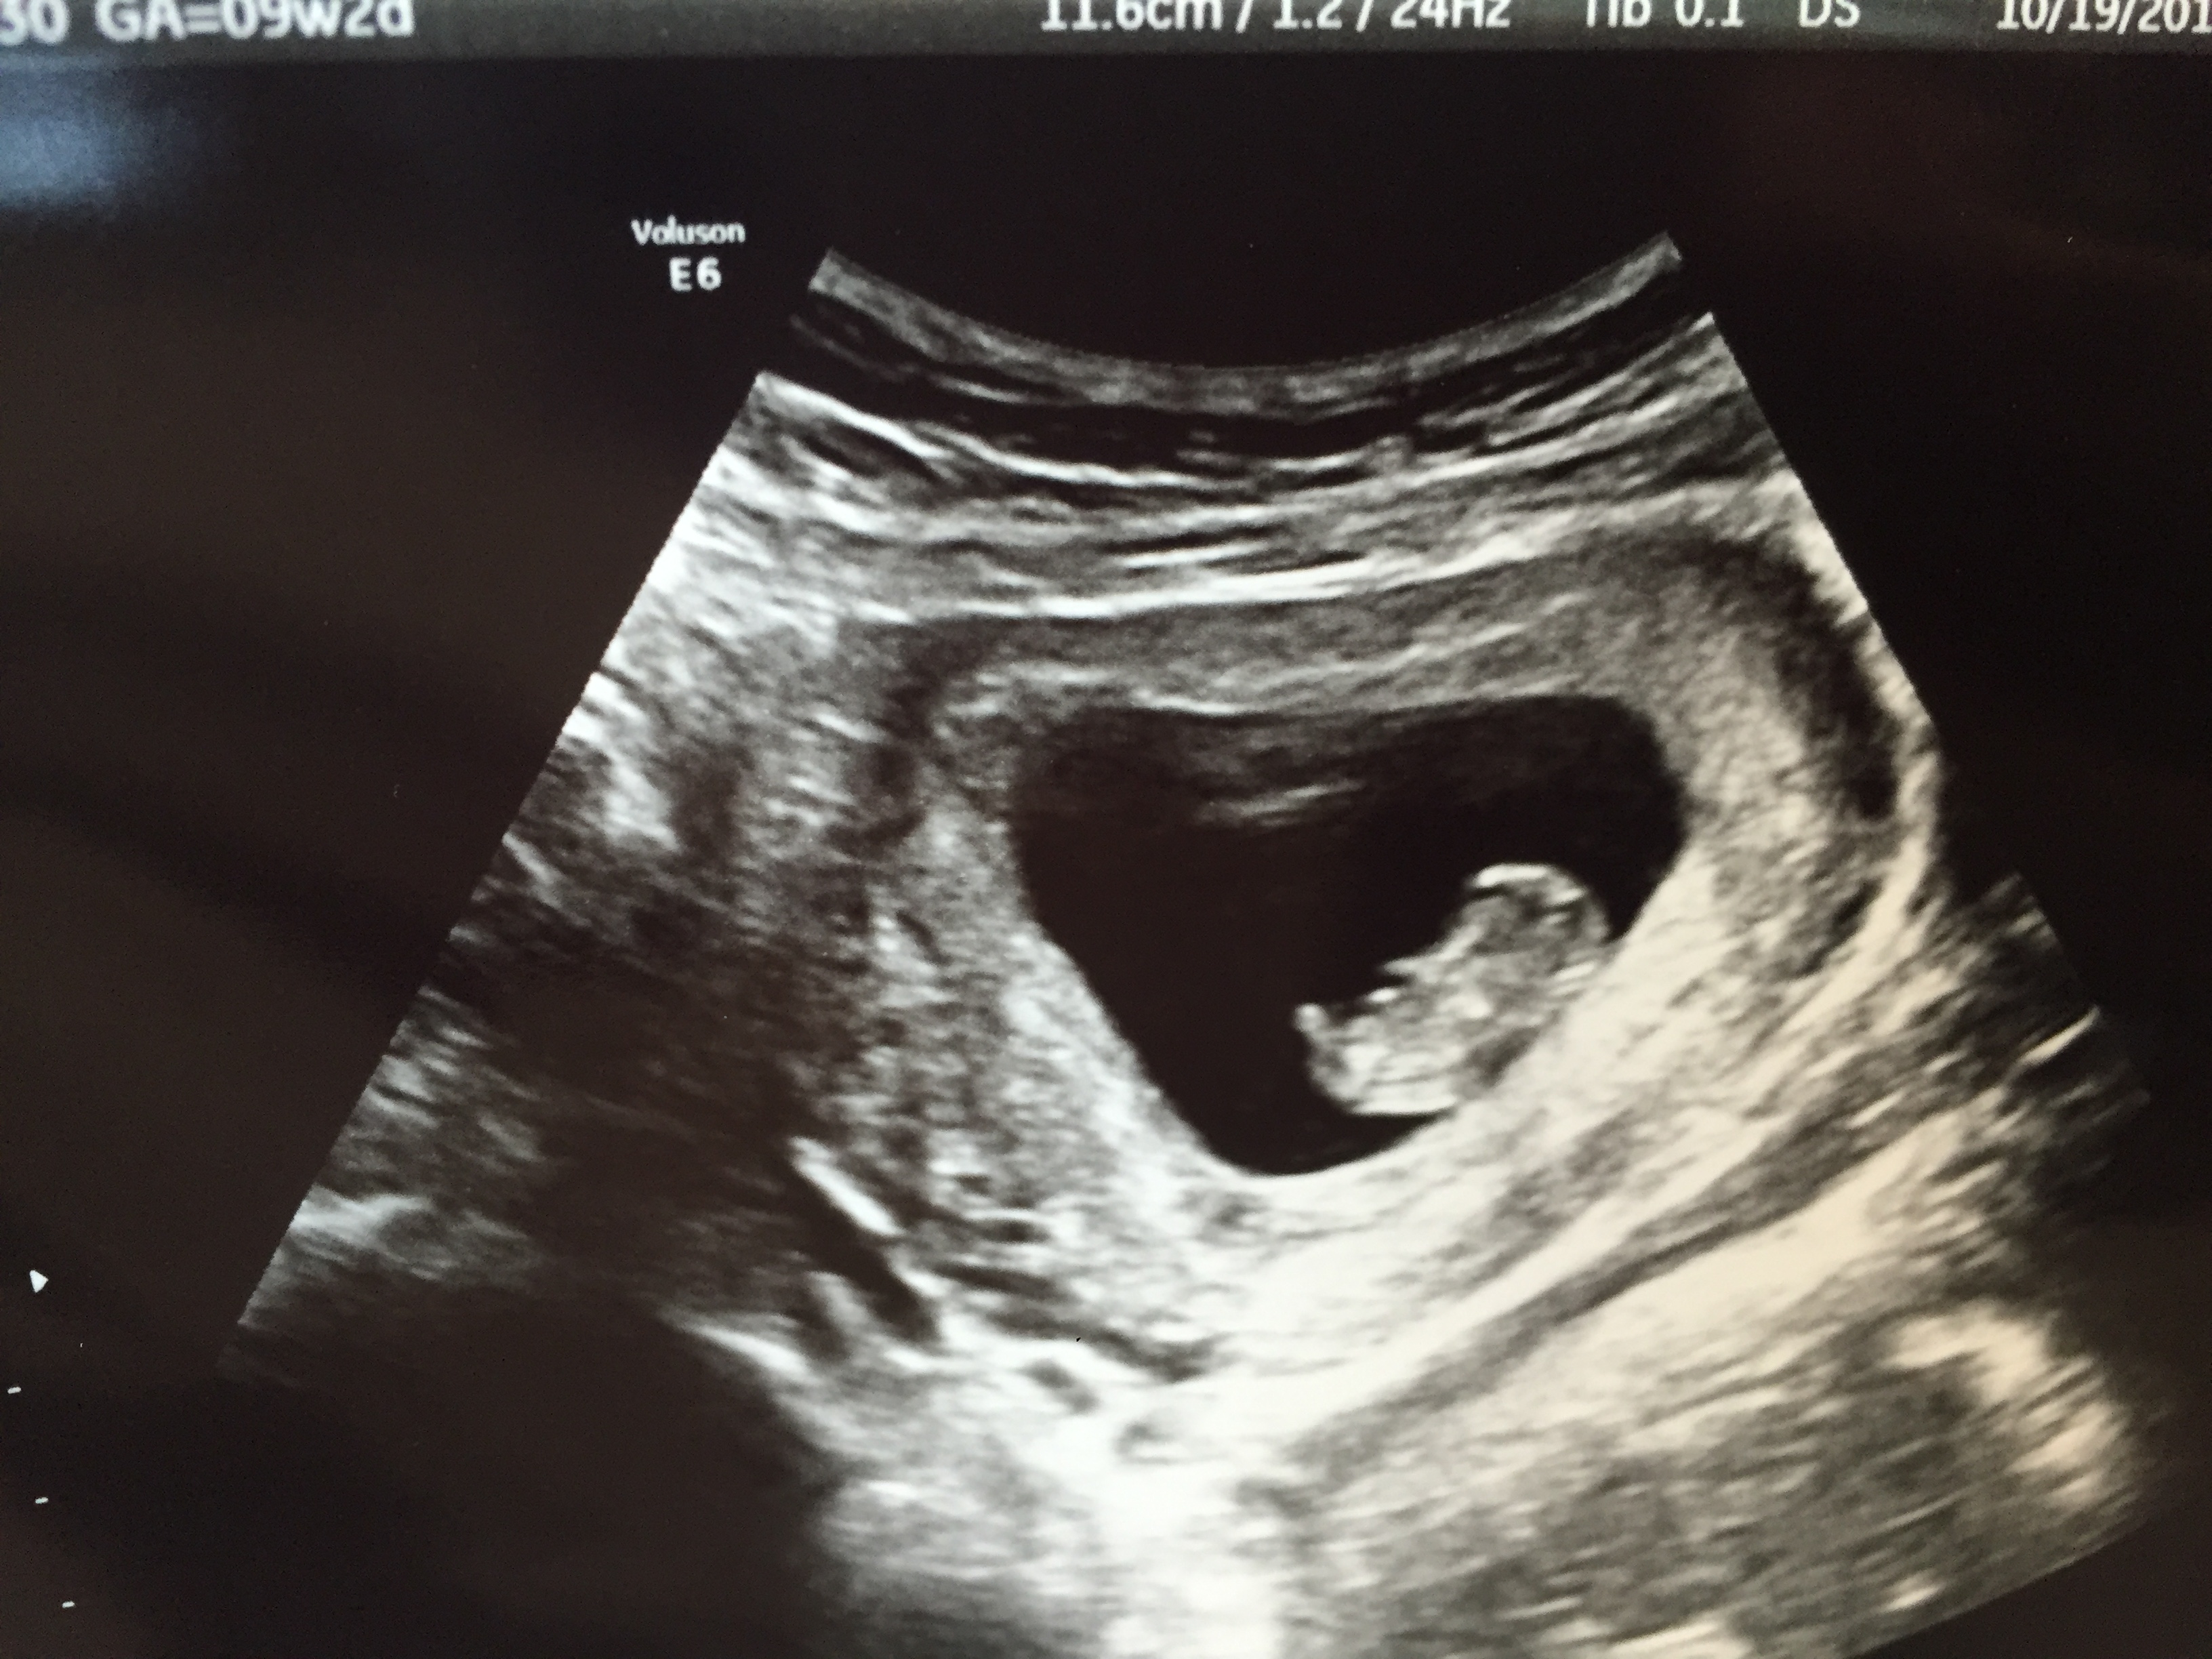

Finally had our ultrasound yesterday. 9 weeks exactly! HB is 163 BPM. I was so nervous walking into that room that something may have been wrong. I am so thankful and feel so blessed that our baby is healthy! :x :x